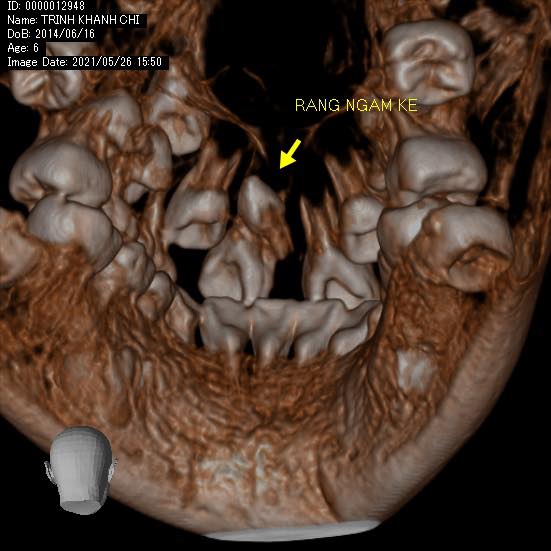

#khớpcắnhở #openbite Dr. Thy Nga Nguyen